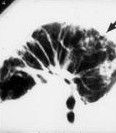

肺間質病的病理改變主要發生在肺泡間隔和鄰近的肺泡中。間質性肺疾病最早的表現為肺泡炎。開始因炎性細胞浸潤,肺泡壁增厚,肺泡腔縮小、閉鎖 型肺泡上皮損傷、消失 型細胞增生。毛細血管內皮細胞也壞變、消失。間質中成纖維細胞增生,膠原積聚,間質纖維變性。顯微鏡下觀察可見到間質水腫、增厚、逐漸纖維化。病情進展,上皮基礎膜破潰,間質成分由此突入肺泡腔,於是正常肺組織結構被破壞,代以纖維化組織,間以殘餘的擴大的肺泡和細支氣管。這是終末期的 ILD肺部表現.即蜂窩肺。

臨床表現 進行性加重的呼吸困難是較為突出的臨床症狀。伴有咳嗽,痰量少或為刺激性乾咳。呼吸道症狀無季節性緩解,常用的祛痰止咳藥物或抗生素效果差,病情多呈緩慢加重。體檢可見呼吸淺速,雙肺部可聽到高音調的細濕 音。重症者可見紫紺。部分患者(如IPF患者)中可見到杵狀指(趾)。胸部 X射線片可見雙肺瀰漫性網狀結節狀陰影。常規肺功能檢查可提供限制性通氣功能障礙和彌散功能降低的證據。